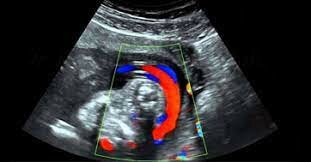

• Doppler

Doppler

Primer equipo a color